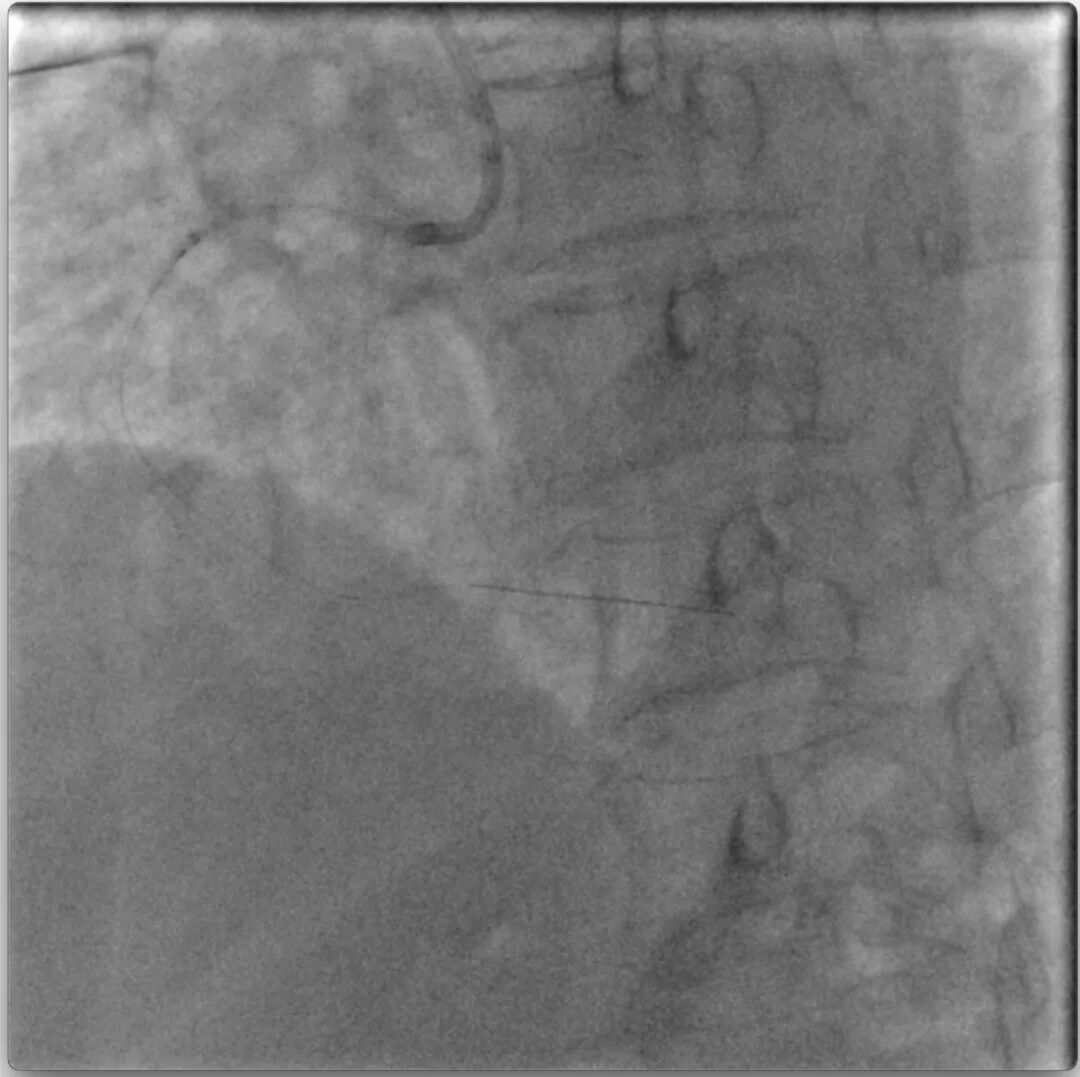

单腔微导管不能跟进严重影响导丝操控,平行进入第二根Pilot200导丝亦不能通过中段次全闭塞,判断中段局部存在严重钙化,只有解决此处钙化困扰才能跟进单腔微导管加强导丝操控或使用双腔微导管平行导丝技术寻找真腔。回撤内膜下Pilot200,通过微导管送入旋磨导丝,使之进入Pilot200造成的内膜下(视频14),但由于旋磨导丝进入长度明显不足,支撑力有限,1.25mm旋磨头仅能在右冠中段阻力点局部小心旋磨,控制旋磨头前进长度,避免支撑系统脱出(视频15)。

虽然旋磨头不能完全通过中段阻力点,但微导管能够较前多跟进2-3mm,且Pilot200操控性明显提高,最终进入右冠远端真腔。随后再次尝试在延长导管支撑下小球囊扩张、使用不同微导管,仍旧无法通过中段阻力病变(图16)。